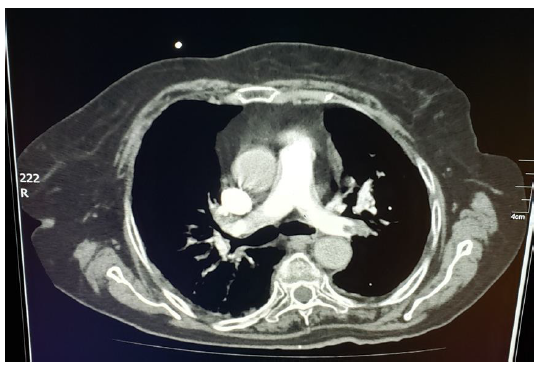

Es valorada por el servicio de Cardiología, que mediante ecocardiograma transtorácico, identifica una imagen de densidad de tejidos blandos, móvil, con un diámetro de 24 x 11 mm, adherido a cuerdas tendinosas en la válvula tricúspide más hipocinesia septal severa, compatible con trombo intracavitario derecho (figura 1). Ante estos hallazgos se sugiere evaluar presunta etiología pulmonar. Se llevó a cabo angiotomografía axial computarizada en la que se observó trombo que ocluye el flujo sanguíneo de arteria pulmonar derecha (figura 2).